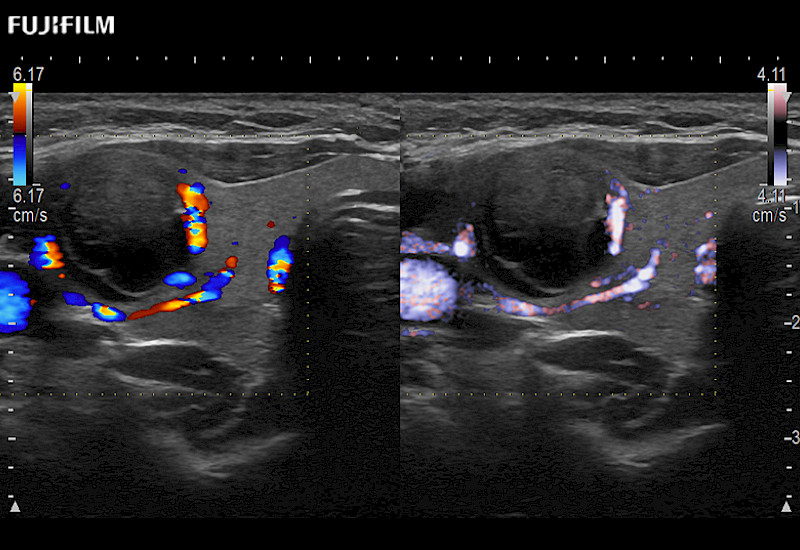

Extraordinary high-resolution digital imaging

Multi-Parametric imaging modalities

Our dedication to Surgical Oncology allows us to offer superior image quality, outstanding system reliability and intuitive use of cutting edge technology.